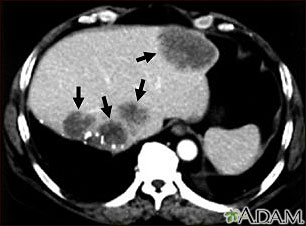

Liver metastases, CT scan

Liver metastases, CT scan

A CT scan of the upper abdomen showing multiple metastasis (cancer that has spread) in the liver of a patient with carcinoma of the large bowel. Note the dark areas in the liver (left side and center of picture).